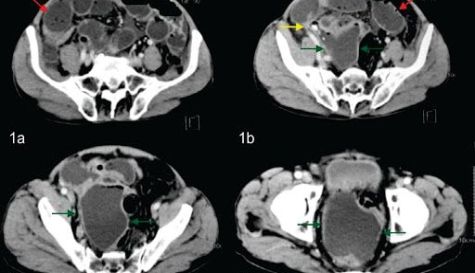

Por su parte la tomografía computada tiene una sensibilidad cercana al 98% y una especificidad que bordea el 100%, permitiendo al radiólogo confirmar este diagnóstico y poder realizar además diversos diagnósticos diferenciales.